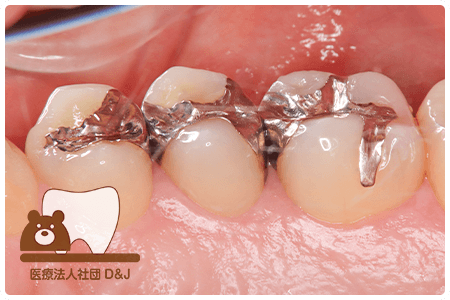

症例8フルジルコニアクラウン

治療前

治療中

治療後

治療前

治療中

治療後

29歳 女性

- 治療内容

- 銀歯からフルジルコニアクラウンへの修復

- 治療期間

- 根の治療含め3か月

- 費用

- 自費

フルジルコニアクラウン:77,000円(税込)

- その他の治療の費用は含まれておりません。

- リスク・副作用

- 強い衝撃が加わると欠けたり割れたりする可能性があります。また、噛み合わせの状態によっては脱離や周囲の歯への影響が出ることもあります。